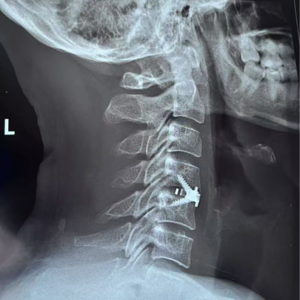

小温回归啦!撒花~这一消失就是两个多月,是因为小温做了颈椎前路手术。如果你也曾感到脖子酸麻、久坐不适,或者你也做过颈椎手术,那这期播客或许能给你一些提醒与陪伴。

00:22 不以为意的频繁落枕,到双手指尖麻痹

03:27 医生对别的患者说,你这个没事儿,他这个可严重了

22:46 术前要做的准备,竟然是扒拉自己的喉管